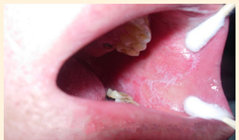

患者钟某,江西新余人,八年检查出口腔扁平苔藓,虽然多次治疗,但病情总是反复发作。一年前经病友介绍从江西赶到广州来我院治疗,来诊时病人口腔左侧可见明显的线状白斑,该处有紧涩感,喝热水也不舒服。在本院治疗三个疗程后,完全康复。

(钟某治疗前)

(钟某治疗后)